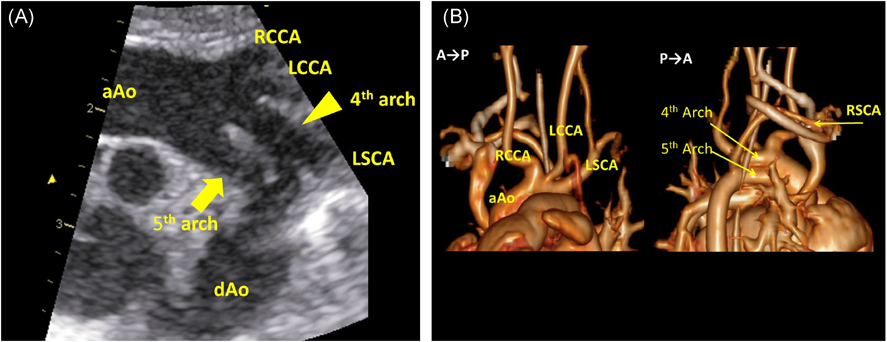

第5大動脈弓遺残を伴った22q11.2重複症候群22q11.2 Duplication Syndrome with Persistent 5th Aortic Arch